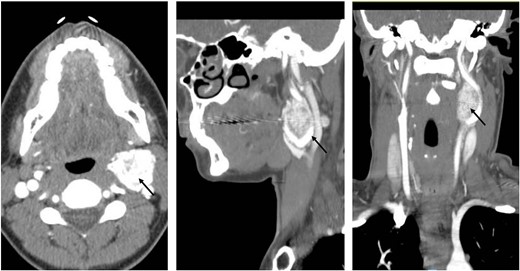

A 35-year-old woman presented with a 6-month history of a progressively enlarging, painless left neck mass. She reported no additional symptoms, including no fevers, night sweats, unexplained weight loss, hoarseness, or dysphagia. She had no significant past medical or family history and did not take any medications. Physical exam revealed a 3-cm well-circumscribed, hard, immovable, and nontender mass on the left lateral neck and no additional abnormalities. A CT scan of the neck and chest was ordered, which revealed a lobulated left cervical mass measuring up to 3.6 cm (Fig. 1). The patient was referred to vascular surgery for further evaluation.

Coronal, sagittal, and axial images showing the 3.6 × 3.5 cm mass splaying the left internal and left external carotid arteries.

A preoperative CTA of the head and neck was done, which revealed a 3.9 × 2.9 × 2.7 cm hypervascular mass centered between the proximal internal and external carotid artery (ECA). The mass completely encased the left ECA and partially (~180°) encased the left internal carotid artery (ICA). Based on these findings, the tumor was classified as category Shamblin II. There were no preoperative hormone labs ordered as in our institution. We do not routinely check for CBTs.